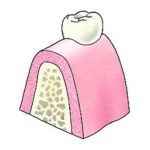

- Het implantaat behoudt de structuur van het bot onder de vervangen tand, aangezien kauwkrachten door het implantaat naar het bot worden overgebracht en het natuurlijke proces van botvernieuwing stimuleert. Het fysiologische proces waardoor de kaak behoorlijk kan ‘slinken’ na het trekken van de tand, wordt hiermee voorkomen. Dit helpt om een goed uiterlijk te behouden – van zowel de herstelde tand als het gelaat.

Wanneer een tand of een kies wordt getrokken, zal het kaakbot gaan slinken. De kaak wordt smaller, maar ook lager. Implantaten moeten mede afhankelijk van de botkwaliteit en de hoeveelheid krachten die ze te verduren krijgen, een minimale lengte hebben. De beschikbare bothoogte -en breedte is afhankelijk van de grootte van de kaak maar andere structuren zoals o.a. zenuwen, bloedvaten of kaakbijholtes kunnen de hoogte ook beperken. In het geval van te weinig hoogte in de kaakbijholte kan er nog een procedure worden uitgevoerd waarbij de kaakbijholte wordt opgevuld met bot (sinus-lift).

Het schroefdeel van het implantaat moet volledig in het kaakbot geplaatst worden en in geslonken kaken kan dat niet altijd. De kaak is dan vaak aan de wangzijde te smal geworden waardoor het implantaat daar niet volledig bedekt is met bot. Mocht de kaakwal in de breedte of de hoogte tekort komen wegens deze dimensionale veranderingen dan zal een botherstel operatie worden uitgevoerd om dit op te lossen (Guided Bone Regeneration) . Deze operatie kan vaak tegelijkertijd met het plaatsen van het implantaat worden uitgevoerd.